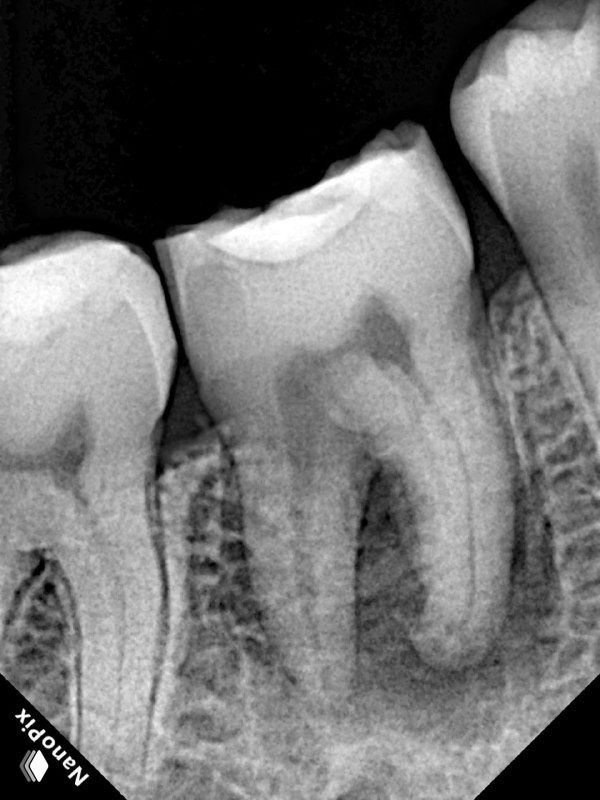

- 1) Обязательно провожу хорошую изоляцию, чтобы была видна полностью коронка зуба. Это важно для создания полости зуба, так как контуры пульпарной камеры повторяют внешние контуры коронки зуба.

- 2) Так как в восьмерках чаще всего сложная анатомия, то стараюсь делать классический доступ. Если позволяет расположение и анатомия, можно и консервативный доступ.

- 3) Для доступа использую шаровидный бор на ножке, длинный цилинд/конус и обязательно алмазную насадку с напылением Eighteeth E3D. Так как доработает полость доступа алмазная насадка, ни один бор сделать не сможет.